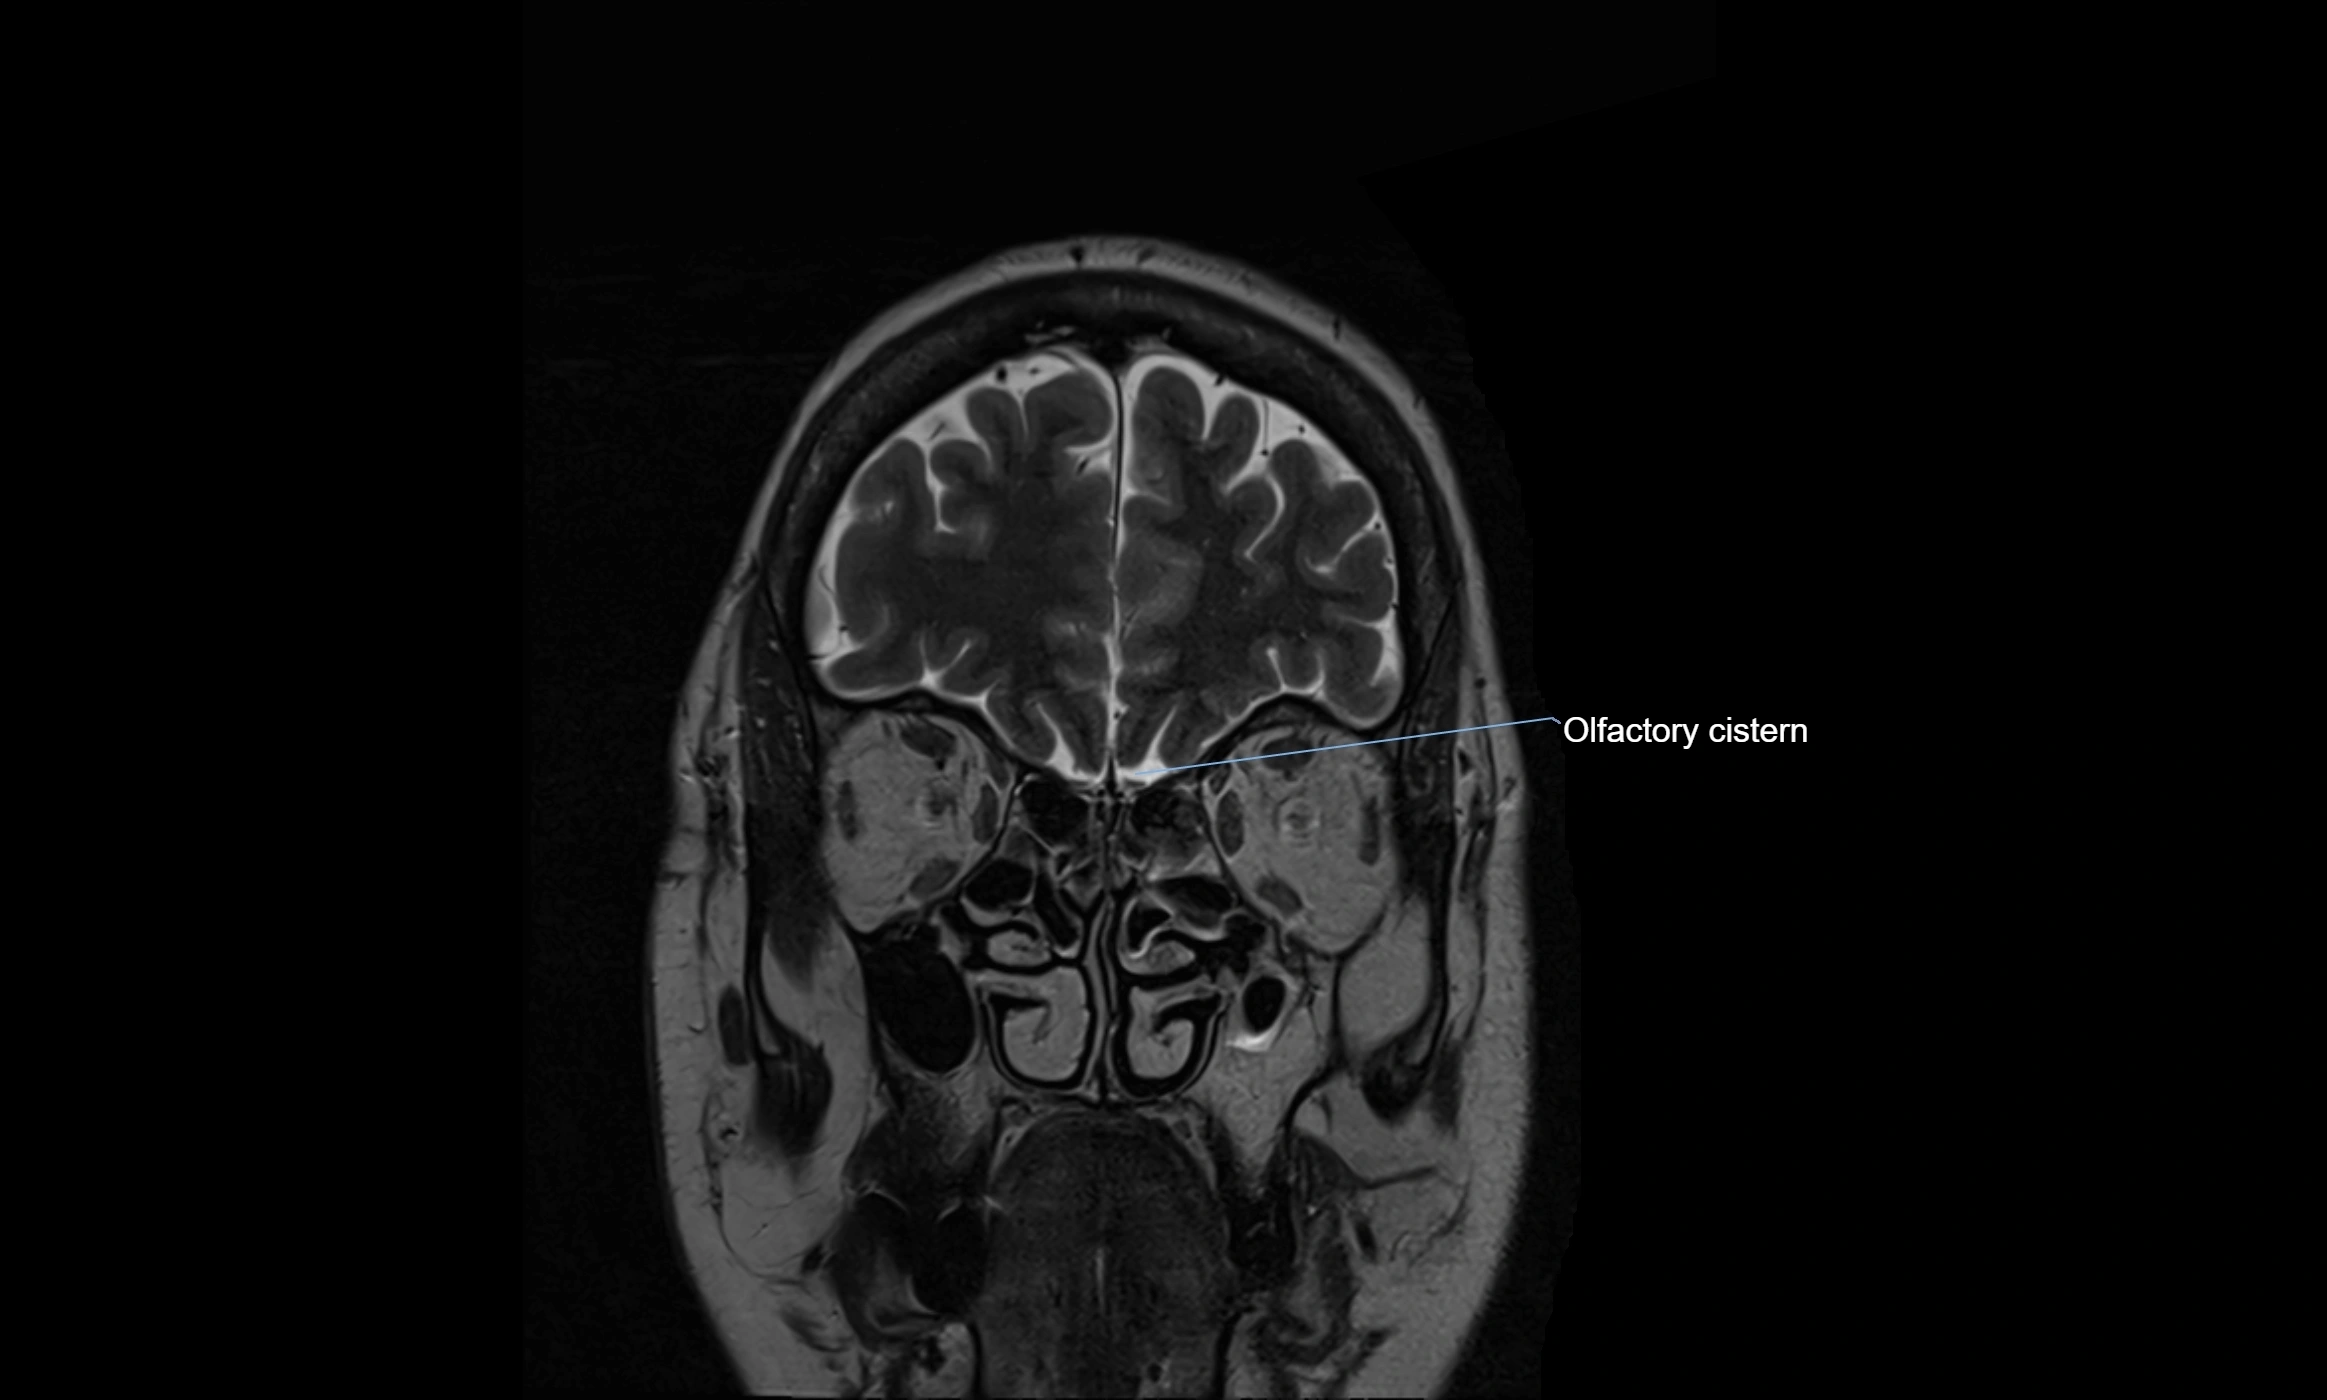

MRI images

image